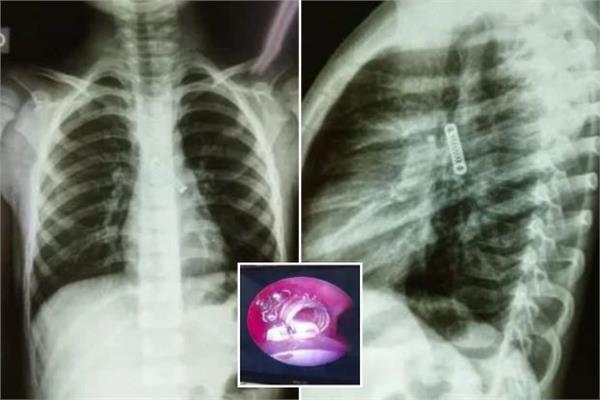

ابتلع صبي عمره 13 عاما نحو 100 مغناطيس اشتراه عبر الإنترنت، مما أجبر الجراحين في نيوزيلندا على إزالة أنسجة تالفة من أمعائه.وبعد معاناته آلاما في البطن استمرت 4 أيام، نقل المراهق، الذي لم يكشف عن اسمه، إلى مستشفى تاورانغا في الجزيرة الشمالية لنيوزيلندا.وجاء في تقرير صادر عن أطباء المستشفى في...